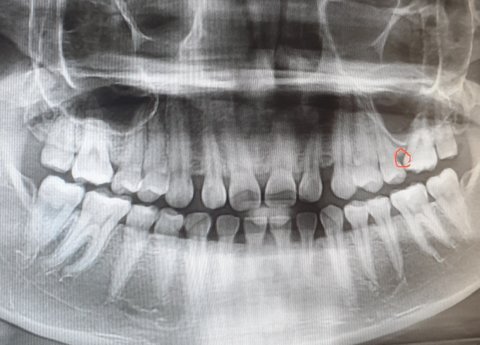

혹시 몰라 엑스레이도 찍어왔는데 뿌리가 긴 편이라고 하더라구요? 긴편인지 아닌지는 저는 모르겠지만요ㅎㅎ 긴 편에 속하는거 맞나요?? 일단 사진 추가 합니다!